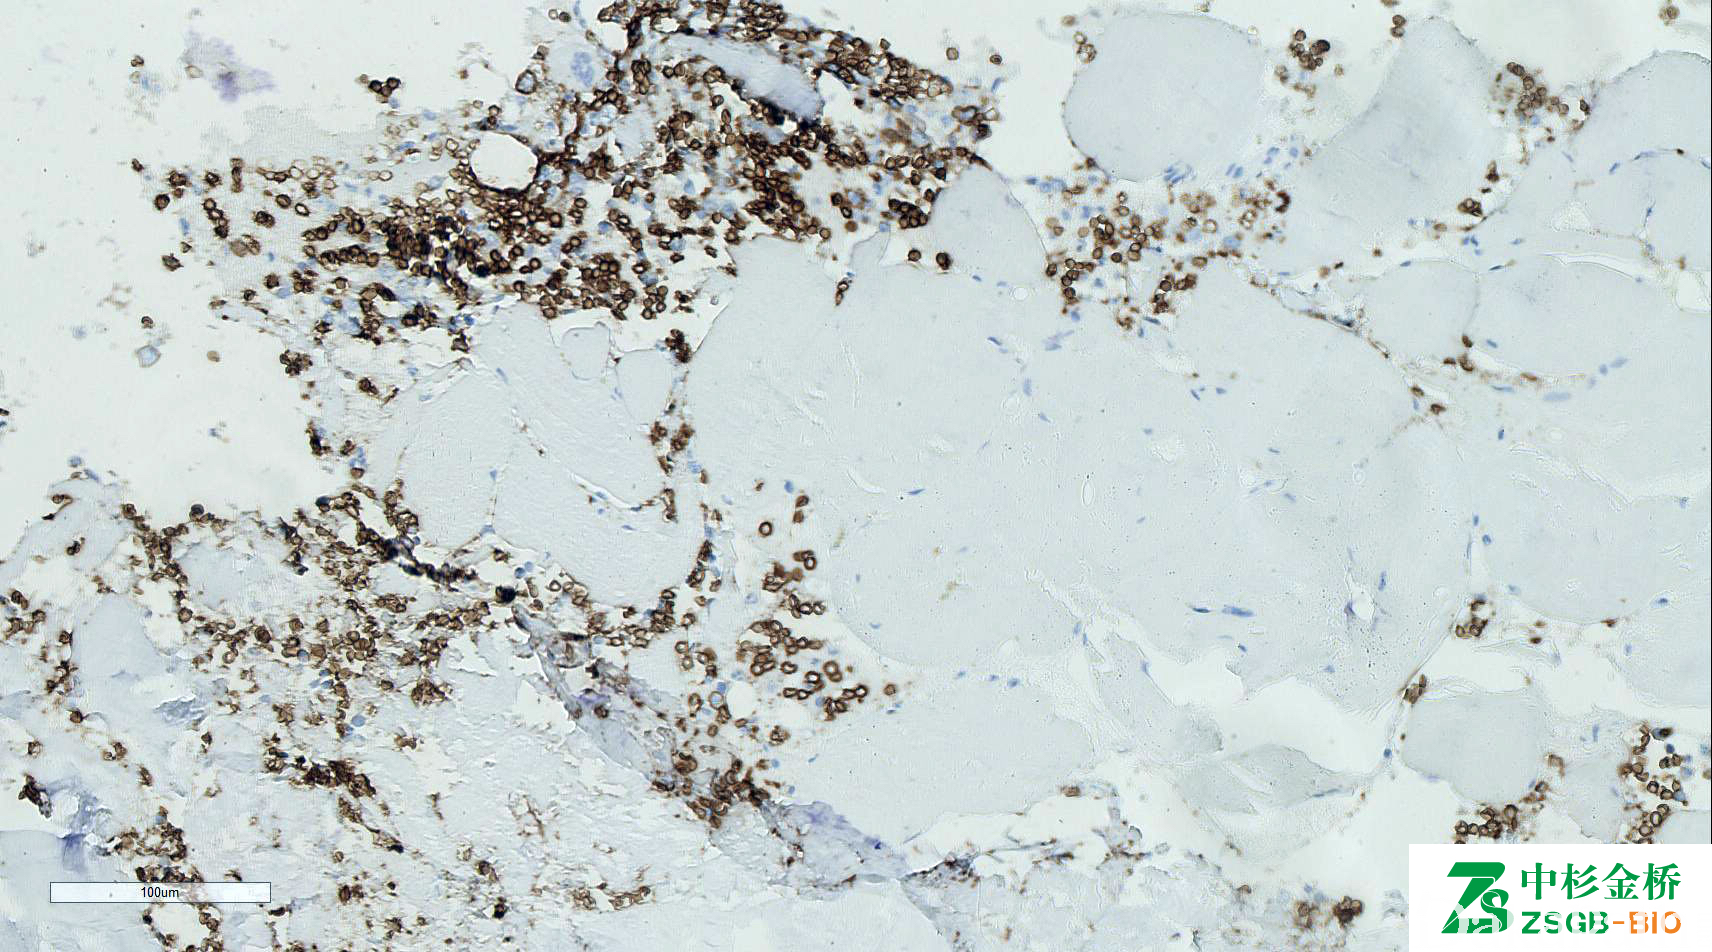

CD235a

人红细胞表面唾液酸糖蛋白,表达于红细胞生成的全过程中,高表 达提示红细胞成熟。

信号定位: 胞膜

红系来源白血病的诊断,敏感性较低,急淋和急粒几乎不表达。